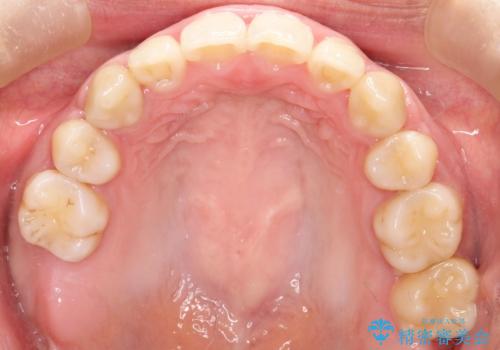

上下の歯のガタガタ ワイヤーでの抜歯矯正で整った歯並びへ

抜歯スペースを使って前歯を引っ込めることにより、口元の突出感も改善できました。